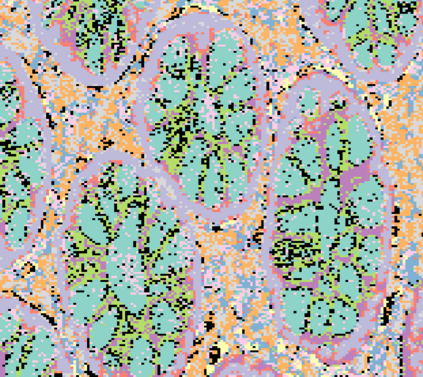

The usage of chemical imaging technologies is becoming a routine accompaniment to traditional methods in pathology. Significant technological advances have developed these next generation techniques to provide rich, spatially resolved, multidimensional chemical images. The rise of digital pathology has significantly enhanced the synergy of these imaging modalities with optical microscopy and immunohistochemistry, enhancing our understanding of the biological mechanisms and progression of diseases. Techniques such as imaging mass cytometry provide labelled multidimensional (multiplex) images of specific components used in conjunction with digital pathology techniques. These powerful techniques generate a wealth of high dimensional data that create significant challenges in data analysis. Unsupervised methods such as clustering are an attractive way to analyse these data, however, they require the selection of parameters such as the number of clusters. Here we propose a methodology to estimate the number of clusters in an automatic data-driven manner using a deep sparse autoencoder to embed the data into a lower dimensional space. We compute the density of regions in the embedded space, the majority of which are empty, enabling the high density regions to be detected as outliers and provide an estimate for the number of clusters. This framework provides a fully unsupervised and data-driven method to analyse multidimensional data. In this work we demonstrate our method using 45 multiplex imaging mass cytometry datasets. Moreover, our model is trained using only one of the datasets and the learned embedding is applied to the remaining 44 images providing an efficient process for data analysis. Finally, we demonstrate the high computational efficiency of our method which is two orders of magnitude faster than estimating via computing the sum squared distances as a function of cluster number.